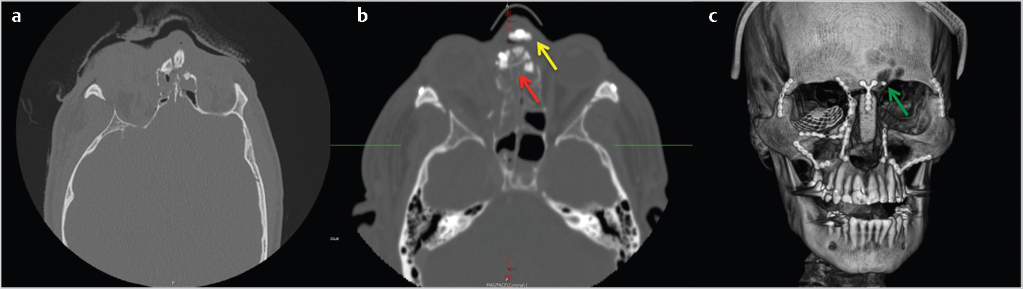

Zygomaticomaxillary Complex (ZMC) fractures are the most common midface fracture. The ZMC is a tetrapod structure with articulations classically described in four areas: (1) the zygomaticomaxillary buttress (ZMB), (2) the infraorbital rim (IOR), (3) the frontozygomatic suture (FZ), and (4) the zygomatic arch (ZA). The fifth articulation, and most reliable in determination of adequate reduction, is the zygomaticosphenoid suture (ZSS). The ZMC fracture propagates through the floor and lateral walls of the orbit (Fig. 19‑4).

With the advent of CT scans, orbital exploration when treating ZMC fractures decreased from 90 to 30% in the late 1980s. 18 Surgical exploration and repair of orbital wall fractures center around function (diplopia) which cannot be fully determined at the time of repair. Evaluation of entrapment with a forced duction test is mandatory after reduction of the ZMC. The presence of entrapment or significant enophthalmos are indications for orbital exploration. Preoperative CT evaluation with greater that 50% of the floor fractured with soft-tissue herniation has been advocated as a guideline for repair of the floor. 19 In general, low-energy fractures involving isolated articulations do not require orbital exploration. High-energy ZMC fractures often require orbital exploration and repair (Fig. 19‑5).

Rotation of the ZMC, in addition to displacement, creates challenges to ensure appropriate reduction. Axial rotation of the complex around any articulation may demonstrate adequate reduction at an isolated articulation, while globally the ZMC is still significantly displaced. The zygomaticosphenoid suture (ZSS) is the longest line of fracture and provides the most reliable indication of adequate reduction. The frontozygomatic suture does not reliably demonstrate adequate reduction of the ZMC due to ease of rotation of the complex around one point. Open evaluation of at least 3 points of articulation is typically recommended in significantly displaced medium and all high-energy fractures. Utilization of a Carroll-Girard screw or a Rowe elevator can be useful in mobilization of the ZMC.